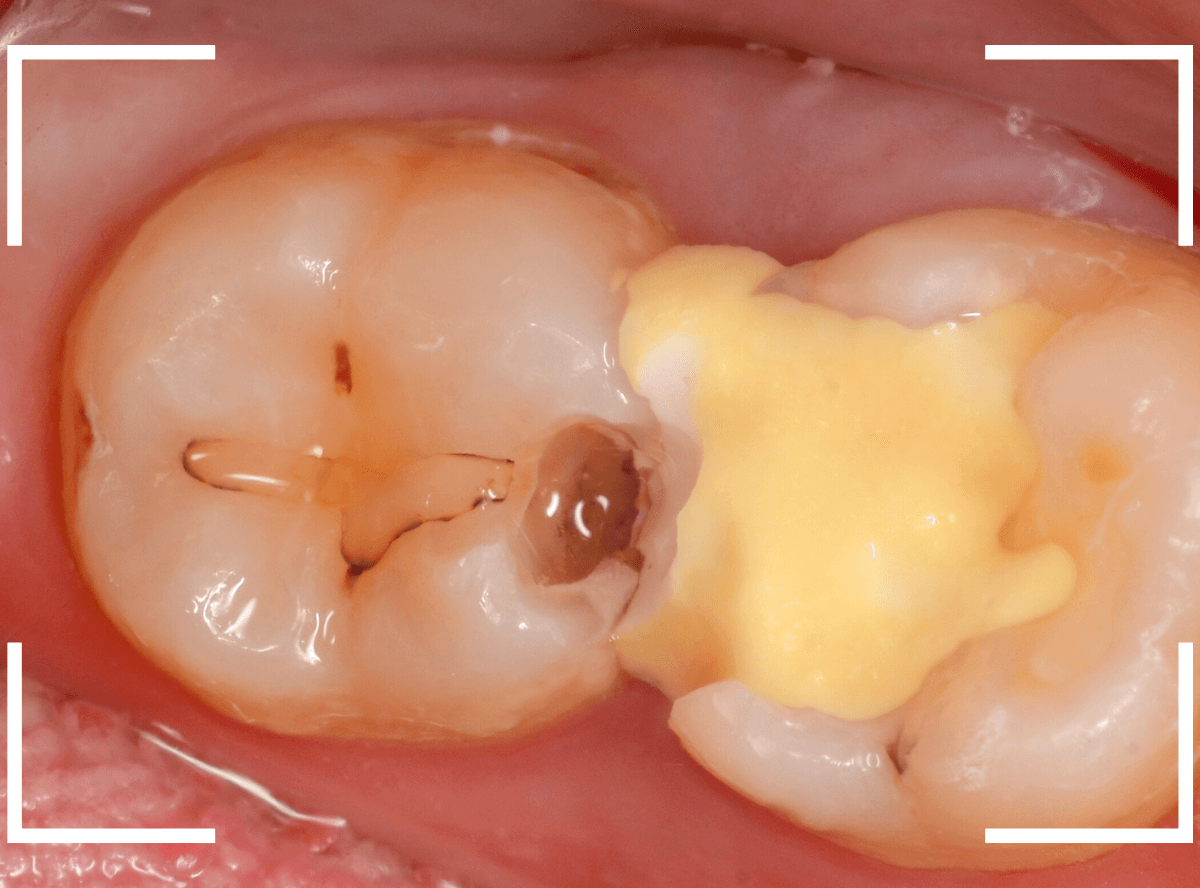

Case.23 歯のすきまから両側が大きな虫歯

「下の奥歯が痛む」という訴えで来院された患者さんのケースです。

目視でも、手前の奥歯がかけていて、中で虫歯が広がってるであろうことは予想できます。

ピンセットで歯を叩いてみても、手前の奥歯が痛むようです。

レントゲン写真で確認します。

青い線が神経、赤い線が虫歯の範囲です。

奥歯の方がより深い虫歯に見えますが、再度打診で確認したところ、やはり手前の奥歯が痛むそうです。

状況から、まず手前の奥歯から治療となりました。

麻酔をして、手前の奥歯のレジンを慎重に外します。

前に虫歯の治療をした時点で、神経スレスレの状態でしたので、削りすぎないように慎重にレジンを外さなければいけません。

レジンを外して、う蝕検知液で確認します。

レジンの中で虫歯が進行していたのがわかります。

慎重に全ての虫歯を除去しました。

何とか、神経が露出せずに済んでいます。

お薬をつめて、セメントで蓋をして経過観察します。